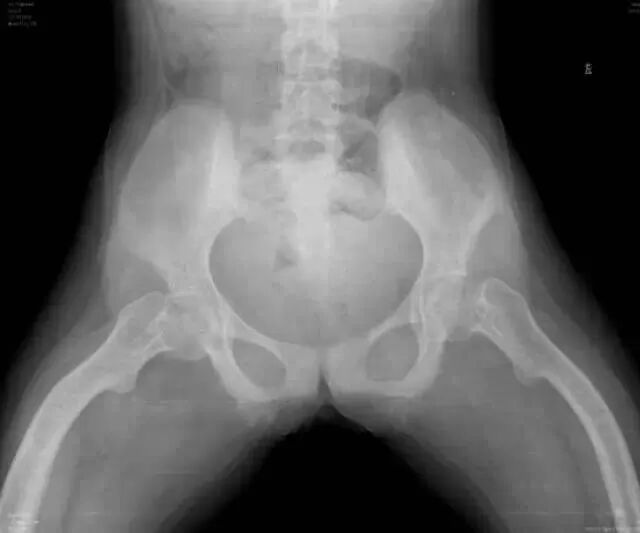

OI标志性特征是骨质脆弱反复骨折, 典型骨骼X线表现(见图二);成骨不全症的临床表现不仅限于骨骼,还常常累及其他结缔组织如眼、耳、皮肤、牙齿等(见图三)。根据临床表型, 澳洲悉尼大学的Sillence教授将OI 分成至Ⅰ-Ⅳ型[7]: Ⅰ型病情最轻, 最常见; Ⅱ最重, 通常围产期致死; Ⅲ型是存活者中最严重的, 常常身材矮小, 呈进行性骨骼畸形; Ⅳ型严重度介于Ⅰ型与Ⅲ型之间。近期发现的Ⅴ型OI 具有肥厚性骨痂、桡骨头脱位、前臂骨间膜钙化、桡骨干骺端下密集骺线等独特临床表现(见图四)。

c. 骨盆平片显示严重的股骨近端髋内翻畸形以及基本完全愈合的转子下骨折;骨折愈合一般从内侧(压应力侧)开始,而骨折不愈合通常发生外侧表面(张应力侧);